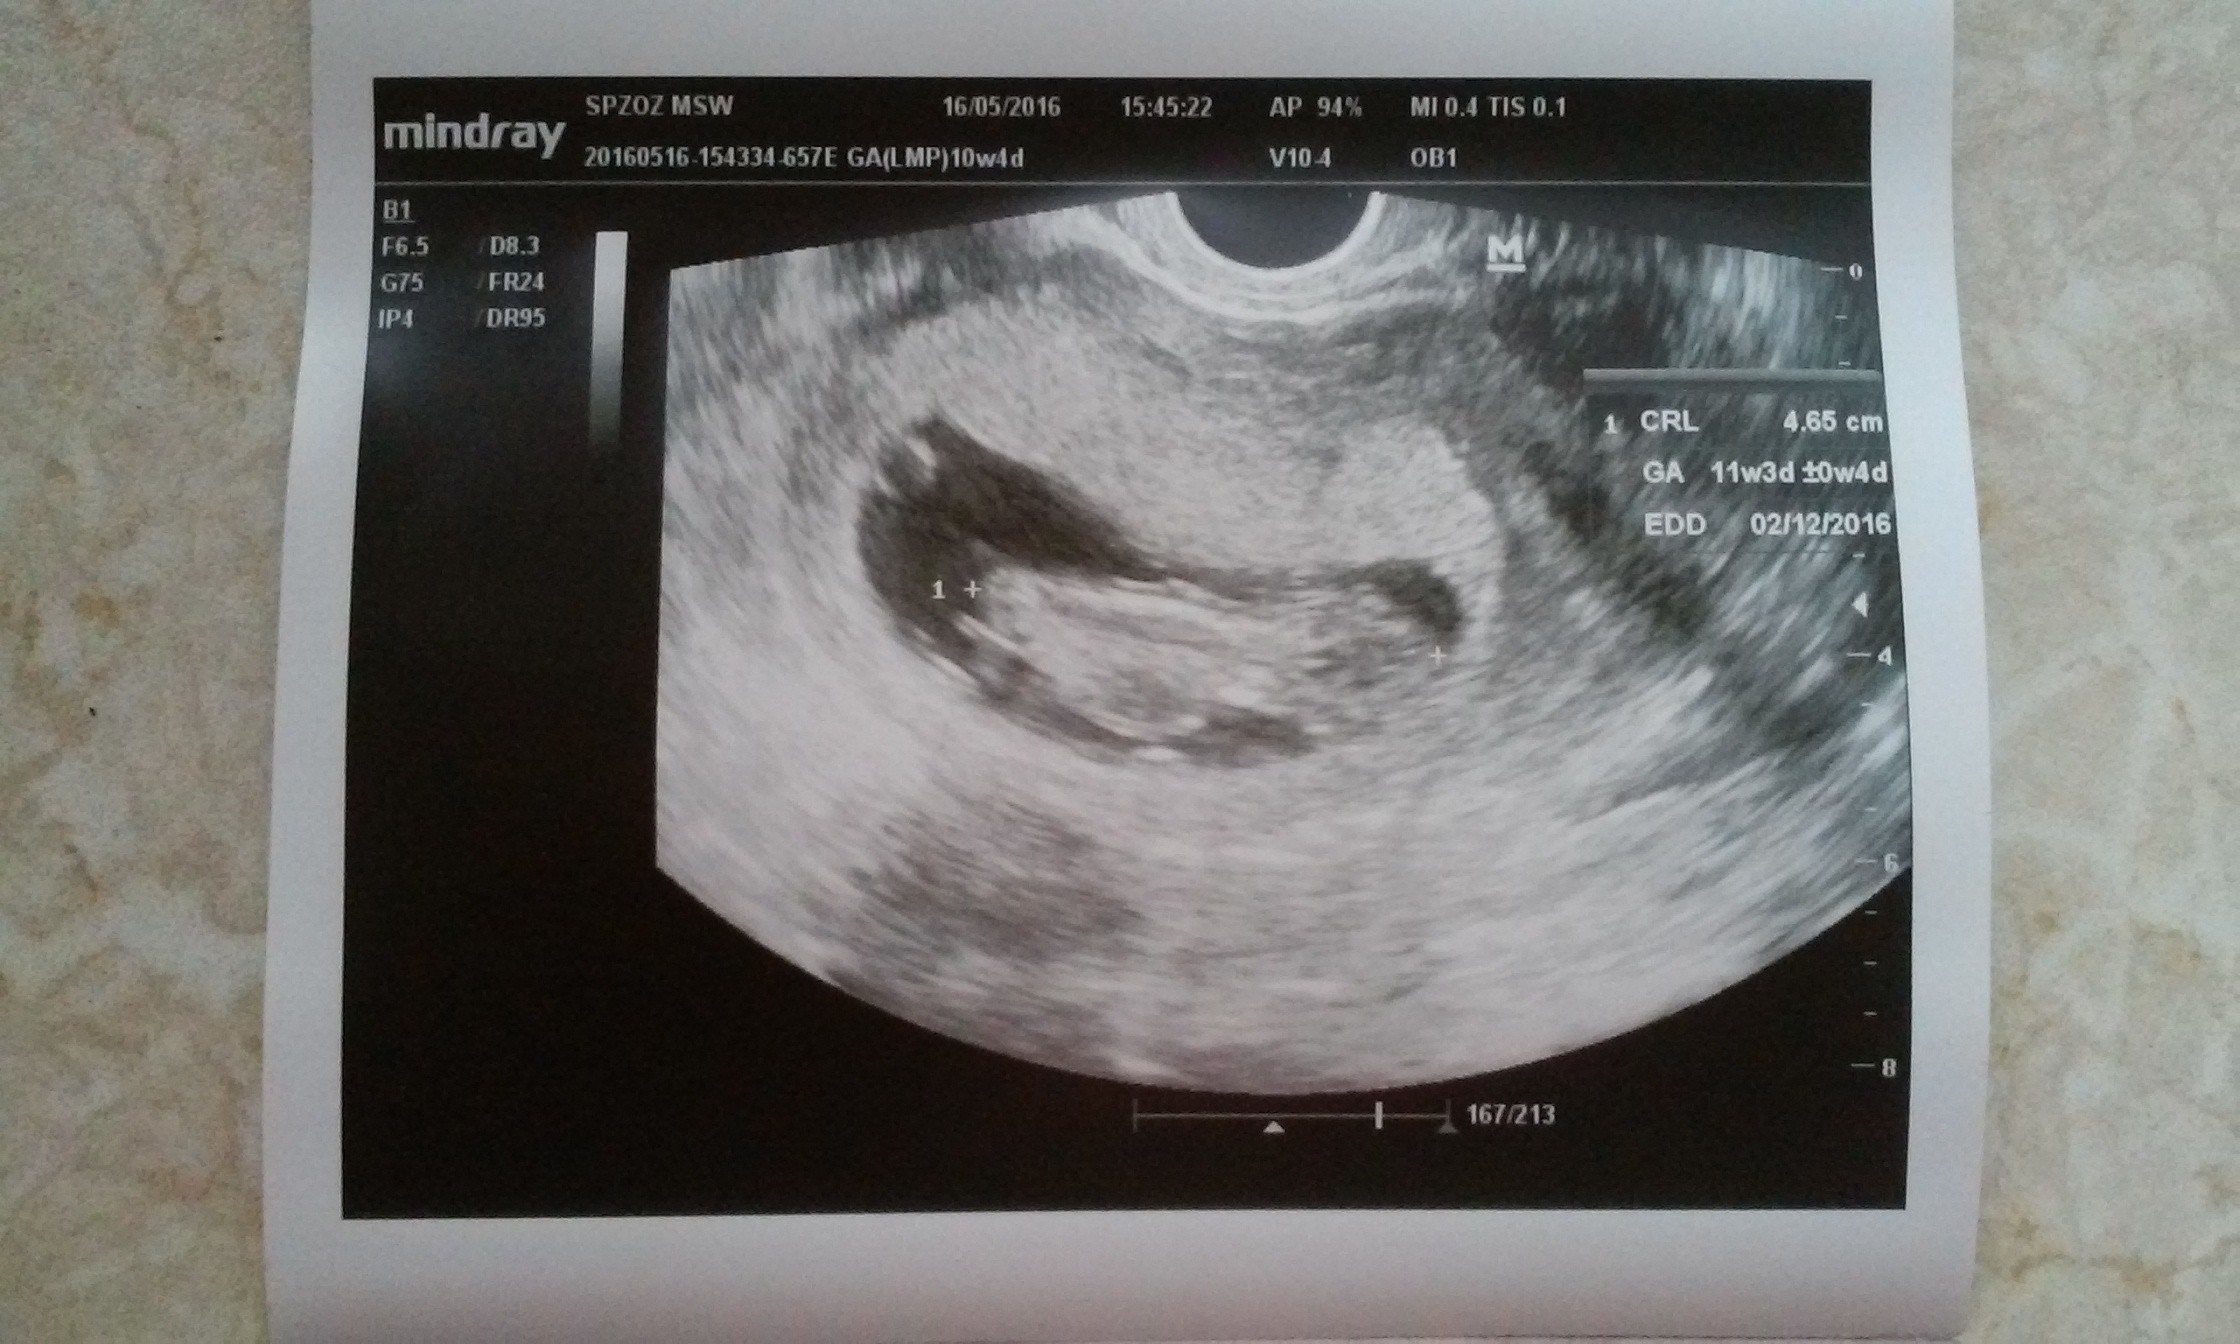

Dla dodania otuchy ta dam ! Wlasnie zobaczylam, ze termin mi sie na usg przesunal z 10 grudnia na 2 grudnia !